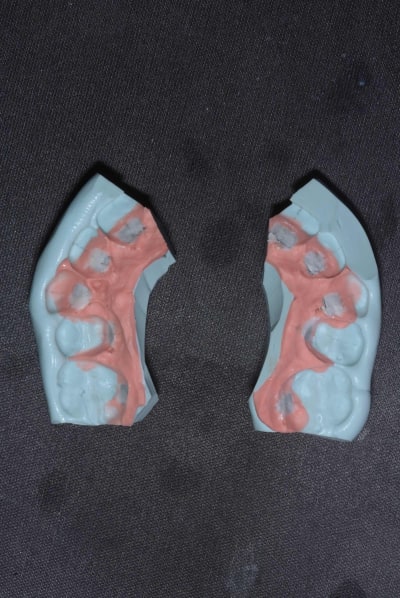

Un petit cas qui montre bien le coté pratique des 2D au niveau de la mise en oeuvre comparé à un appareillage 3D.

Patient qui n'arrivait pas à parler correctement après près de 4 mois avec des 3D. Lui ça ne le dérangé pas trop mais mois si .

Mécaniquement le haut je pense pouvoir traiter avec des 2D sans soucis.

1 retirer l'appareillage en haut, nettoyer prendre une empreinte à l'alginate

2 Couler le plâtre et mettre une couche de séparateur

3 collage indirect chez mois dans la soirée

4 réalisation du tray de transfert le lendemain matin au Cab ( 5 grosse minutes )

5 collage dans l'après midi entre deux patients ;

Si j'avais voulue changer l'appareillage avec un autre systéme ça aurait était :

1 discuter avec le patient pour lui expliquer qu'il y allait avoir un surcout

2 enlever l'appareillage prendre une emreinte double phase silicone ou scann 3D si vous avez une machine compatible

3 empreinte alginate pour une gouttiére plastique ( oui car le temps que vous receviez le matériel les dents vont bouger ...

4 collage en bouche quelque semaine plus tard

5 croisé les doigts très fort pour que le patient n'ai pas de soucie avec le nouveau matériel.

Bref les 2D permettent une flexibilité et réactivité qui est unique parmis les techniques en lingual et ça a très bas cout.